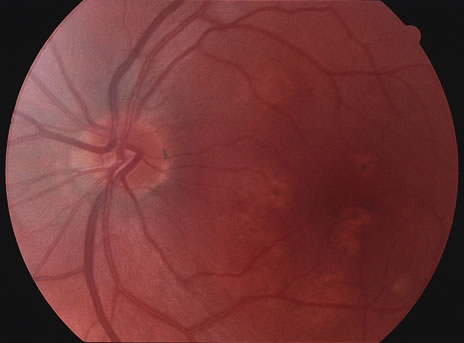

Acutely, there may be creamy white lesions in the posterior pole. These lesions tend to be deep and poorly demarcated. Sometimes these lesions may become confluent. The lesions clear by losing their yellow-white opacification and clearance occurs from centrally to the periphery. With time the lesions resolve leaving mottling of the retinal pigment epithelium (Figs. 5, 6, and 7).

Fig. 6. Fundus photograph of the same case as in Figure 5. The findings at 1 month after the initial presentation now shows mild pigment clumping and mild retinal pigmentary atrophy.

Fig. 7. Fundus photograph of the same case as in Figure 5. The findings at 7 months following initial presentation show more pigment clumping and retinal pigment atrophy in small circular lesions.